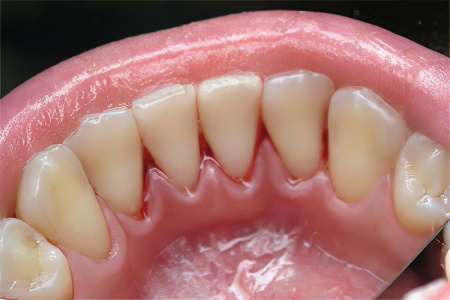

Удаление зубного налёта и камня

При первых признаках пародонтита важно незамедлительно обратиться к стоматологу для профессиональной чистки зубов. Специалист удалит зубной налёт и камень, способствующие воспалительным процессам. Рекомендуется проходить такую чистку не реже одного раза в полгода.

Удаление зубного налёта